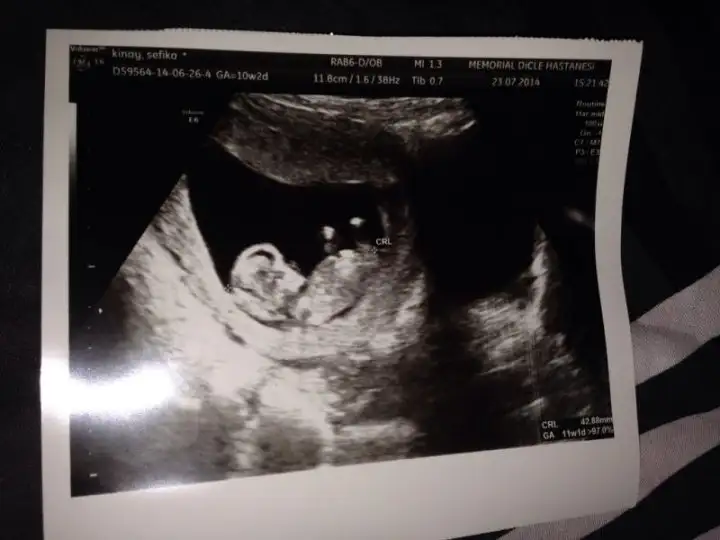

Aslında daha önce sormuştum ama tek bir arkadaş yorum yazdı belki farklı görüşler olur diye tekrar fikir almak istedim :) burda 12+1 iz normalde ama 3 gün önden gidiyoruz 12+4 görünüyor o yüzden minnağım :)

Eki Görüntüle 1214628 %90 kız dedi bir hekim diğer başka hekim birşey söyleyemedi